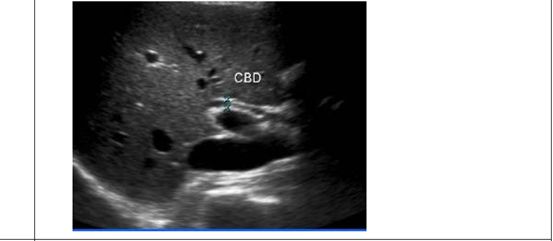

65.下圖為一體檢無症狀病人之腹部超音波圖,箭號所指最可能病灶位置為何?

(C)胰臟

(D)膽囊